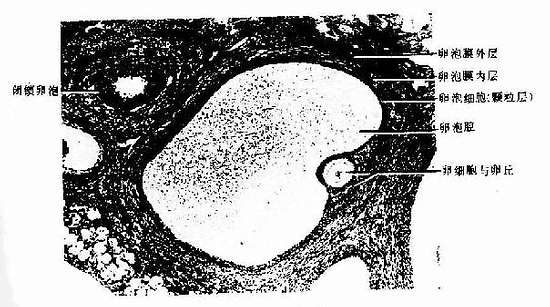

4.成熟卵泡 成熟卵泡(mature follicle)是卵泡发育的最后阶段。卵泡体积很大,直径可达20mm,并向卵巢表面突出(图17-1,17-5)。成熟卵泡的卵泡腔很大,颗粒层甚薄,颗粒细胞也不再增殖。此时的初级卵母细胞又恢复成熟分裂,在排卵前36~48小时完成第一次成熟分裂。产生1个次级卵母细胞(secondary oocyte)和1个很小的第一极体(first polar body)。第一极体位于次级卵母细胞和透明带之间的卵周间隙(perivitelline space)内。次级卵母细胞随即进入第二次成熟分裂,停止于分裂中期。人每个月经周期,可有若干个原始卵泡生长发育,通常只有1个卵泡发育成熟并排卵。

图17-5 猫卵巢内的近成熟卵泡 HE×160

3.次级卵泡 初级卵继续生长成为次级卵泡(secondary follicle),卵泡体积更大,卵泡细胞增至6~12层,细胞间出现一些不规则的腔隙,并逐渐合并成一个半月形的腔,称为卵泡腔(follicullar antrum),腔内充满卵泡液(图17-2)。卵泡液是由卵泡细胞分泌和卵泡膜血管渗出液组成,卵泡液除含有一般营养成分外,还有卵泡分泌的类固醇激素和多种生物活性物质,对卵泡的发育成熟有重要影响。随着卵泡液的增多及卵泡腔扩大,卵母细胞居于卵泡的一侧,并与其周围的颗粒细胞一起突向卵泡腔,形成卵丘(cumulus oophorus)。此时初级卵母细胞直径可达125~150/μm。紧贴透明带的一层柱状卵泡细胞呈放射状排列,称放射冠(corona radiata)。分布在卵泡腔周边的卵泡细胞较小,构成卵泡壁,称为颗粒层(stratum granulosum)。在卵泡生长过程中,卵泡膜分化为内、外两层。内膜层(theca interna)含有较多的多边形或梭形的膜细胞(theca cell)及丰富的毛细血管,膜细胞具有分泌类固醇激素的结构特征。外膜层(theca externa)主要由结缔组织构成,胶原纤维较多,并含有平滑肌纤维。具有卵泡腔的次级卵泡和成熟卵泡又称为囊状卵泡。